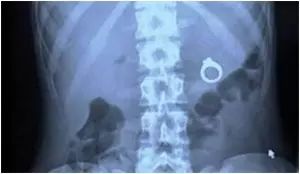

9.一个男的试图用不一样的方式向女友求婚,就把戒指放在了杯子里面……

一个男的试图用不一样的方式向女友求婚,就把戒指放在了杯子里面